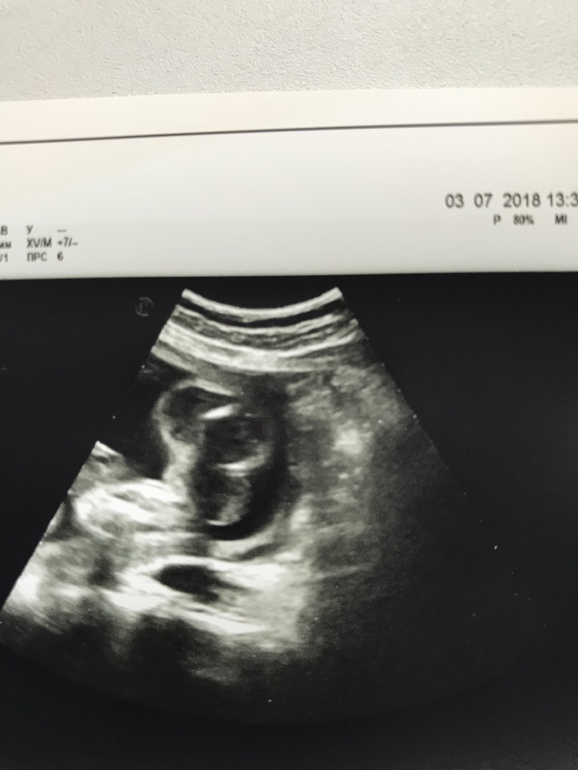

Пол малыша Привет, девочки! У нас неожиданно возникли сложности с определением пола малыша, в 20 недель сказали, что девочка, в 22 (было УЗИ по показаниям), что мальчик, в 29 сказали, что непонятно, то от девочка, то ли мальчик. Я запуталась 😳 Видимо, точно узнаем в сентябре только 😂 Но сейчас интересно порассуждать, как вы думаете, на кого больше похоже на девочку или мальчика? 😊

Я за девочку. На большие половые губы похоже очень. У мальчиков вроде по другому,у меня по крайней мере фото другое было,и уже в 16 недель писюлька четко была мальчишечья)))

Девочка мне кажется. И я согласна с комментарием ниже=) когда мальчик там сразу видно без сомнений, а если вот так сомневаются, то девочка

Я думаю девочка.У мальчиков все таки помощнее что-то должно висеть между ножек.